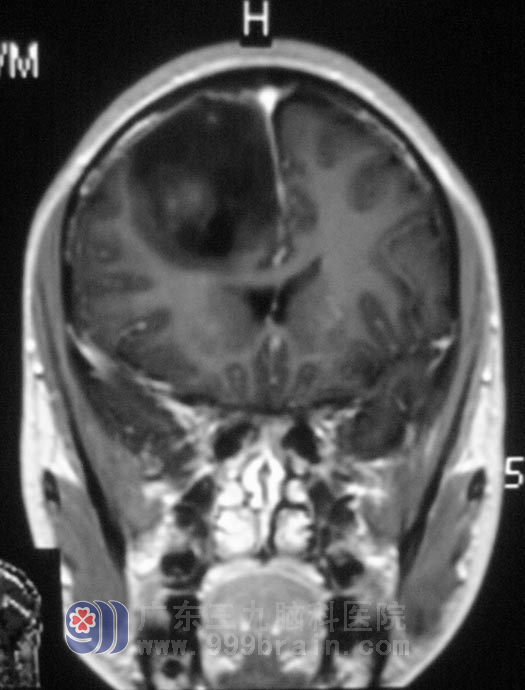

小张在半年前出现失神发作,发作时神志不清,伴有头部左右摇晃,每次持续约30秒到1分钟,当地医院治疗效果欠佳。春节前开始失神发作频率明显增多,每日3次。头部MRI结果显示“右侧额叶占位性病变,考虑胶质瘤可能性大”。

▲手术前